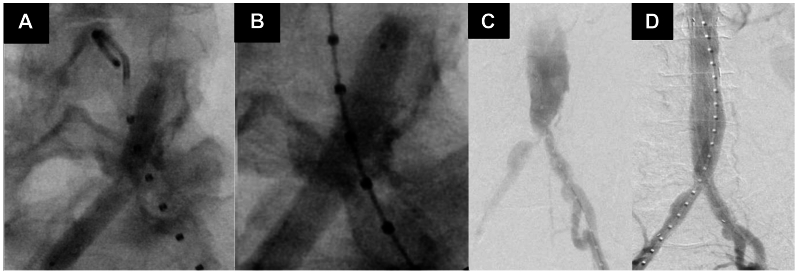

Fig 2.

Intravascular lithotripsy (IVL)-enabled endovascular repair of infrarenal abdominal aortic aneurysm (AAA). A, Pre-IVL angiogram demonstrating kinked vessel contour despite angioplasty. B, Angiogram revealing vessel expansion with angioplasty in conjunction with IVL. C, Fluoroscopy before IVL demonstrating a narrowed aortic bifurcation and stenotic right and left iliac arteries. D, Fluoroscopy after IVL revealing vessel expansion with angioplasty in conjunction with IVL.

A total of 180 pulses of lithotripsy were delivered to the right common iliac artery. Imaging after IVL revealed more favorable vessel expansion. A 12F sheath was then placed directly into the infrarenal aorta without difficulty. From the left side, the 8F sheath was then upsized to a 16F sheath. The main body device of a Gore Excluder endoprosthesis (23 × 12 × 16-mm device) was inserted. On the contralateral side, a 12 × 14 × 100-mm limb was placed, landing just proximal to the iliac bifurcation. Two 8-mm balloons were simultaneously inflated at the device flow divider and the proximal portions of the common iliac arteries bilaterally. A completion angiogram revealed the absence of type I and III endoleaks. However, there was evidence of a delayed type II endoleak. The left side was closed using the previously placed ProGlide sutures. After sheath removal, the right common femoral artery was closed surgically. The patient was taken to the intensive care unit for monitoring after the procedure.